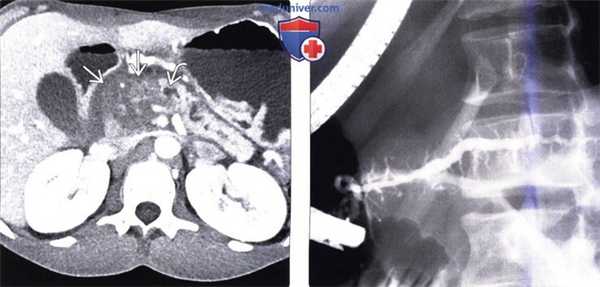

(Слева) На аксиальной КТ с контрастным усилением у пациента, страдающего хроническим панкреатитом, в поджелудочной железе визуализируется гиподенсное объемное образование инфильтративного характера, приводящее к расширению вышележащих отделов панкреатического протока. В паренхиме поджелудочной железы были обнаружены немногочисленные кальцинаты (не продемонстрированы). Была выполнена операция Уиппла, обнаружилось, что образование является фиброзно-воспалительным и обусловлено хроническим панкреатитом.

(Справа) На рентгенограмме (ЭРХПГ) визуализируется неравномерно расширенный главный панкреатический проток и его боковые ветви, что является характерным признаком хронического панкреатита.